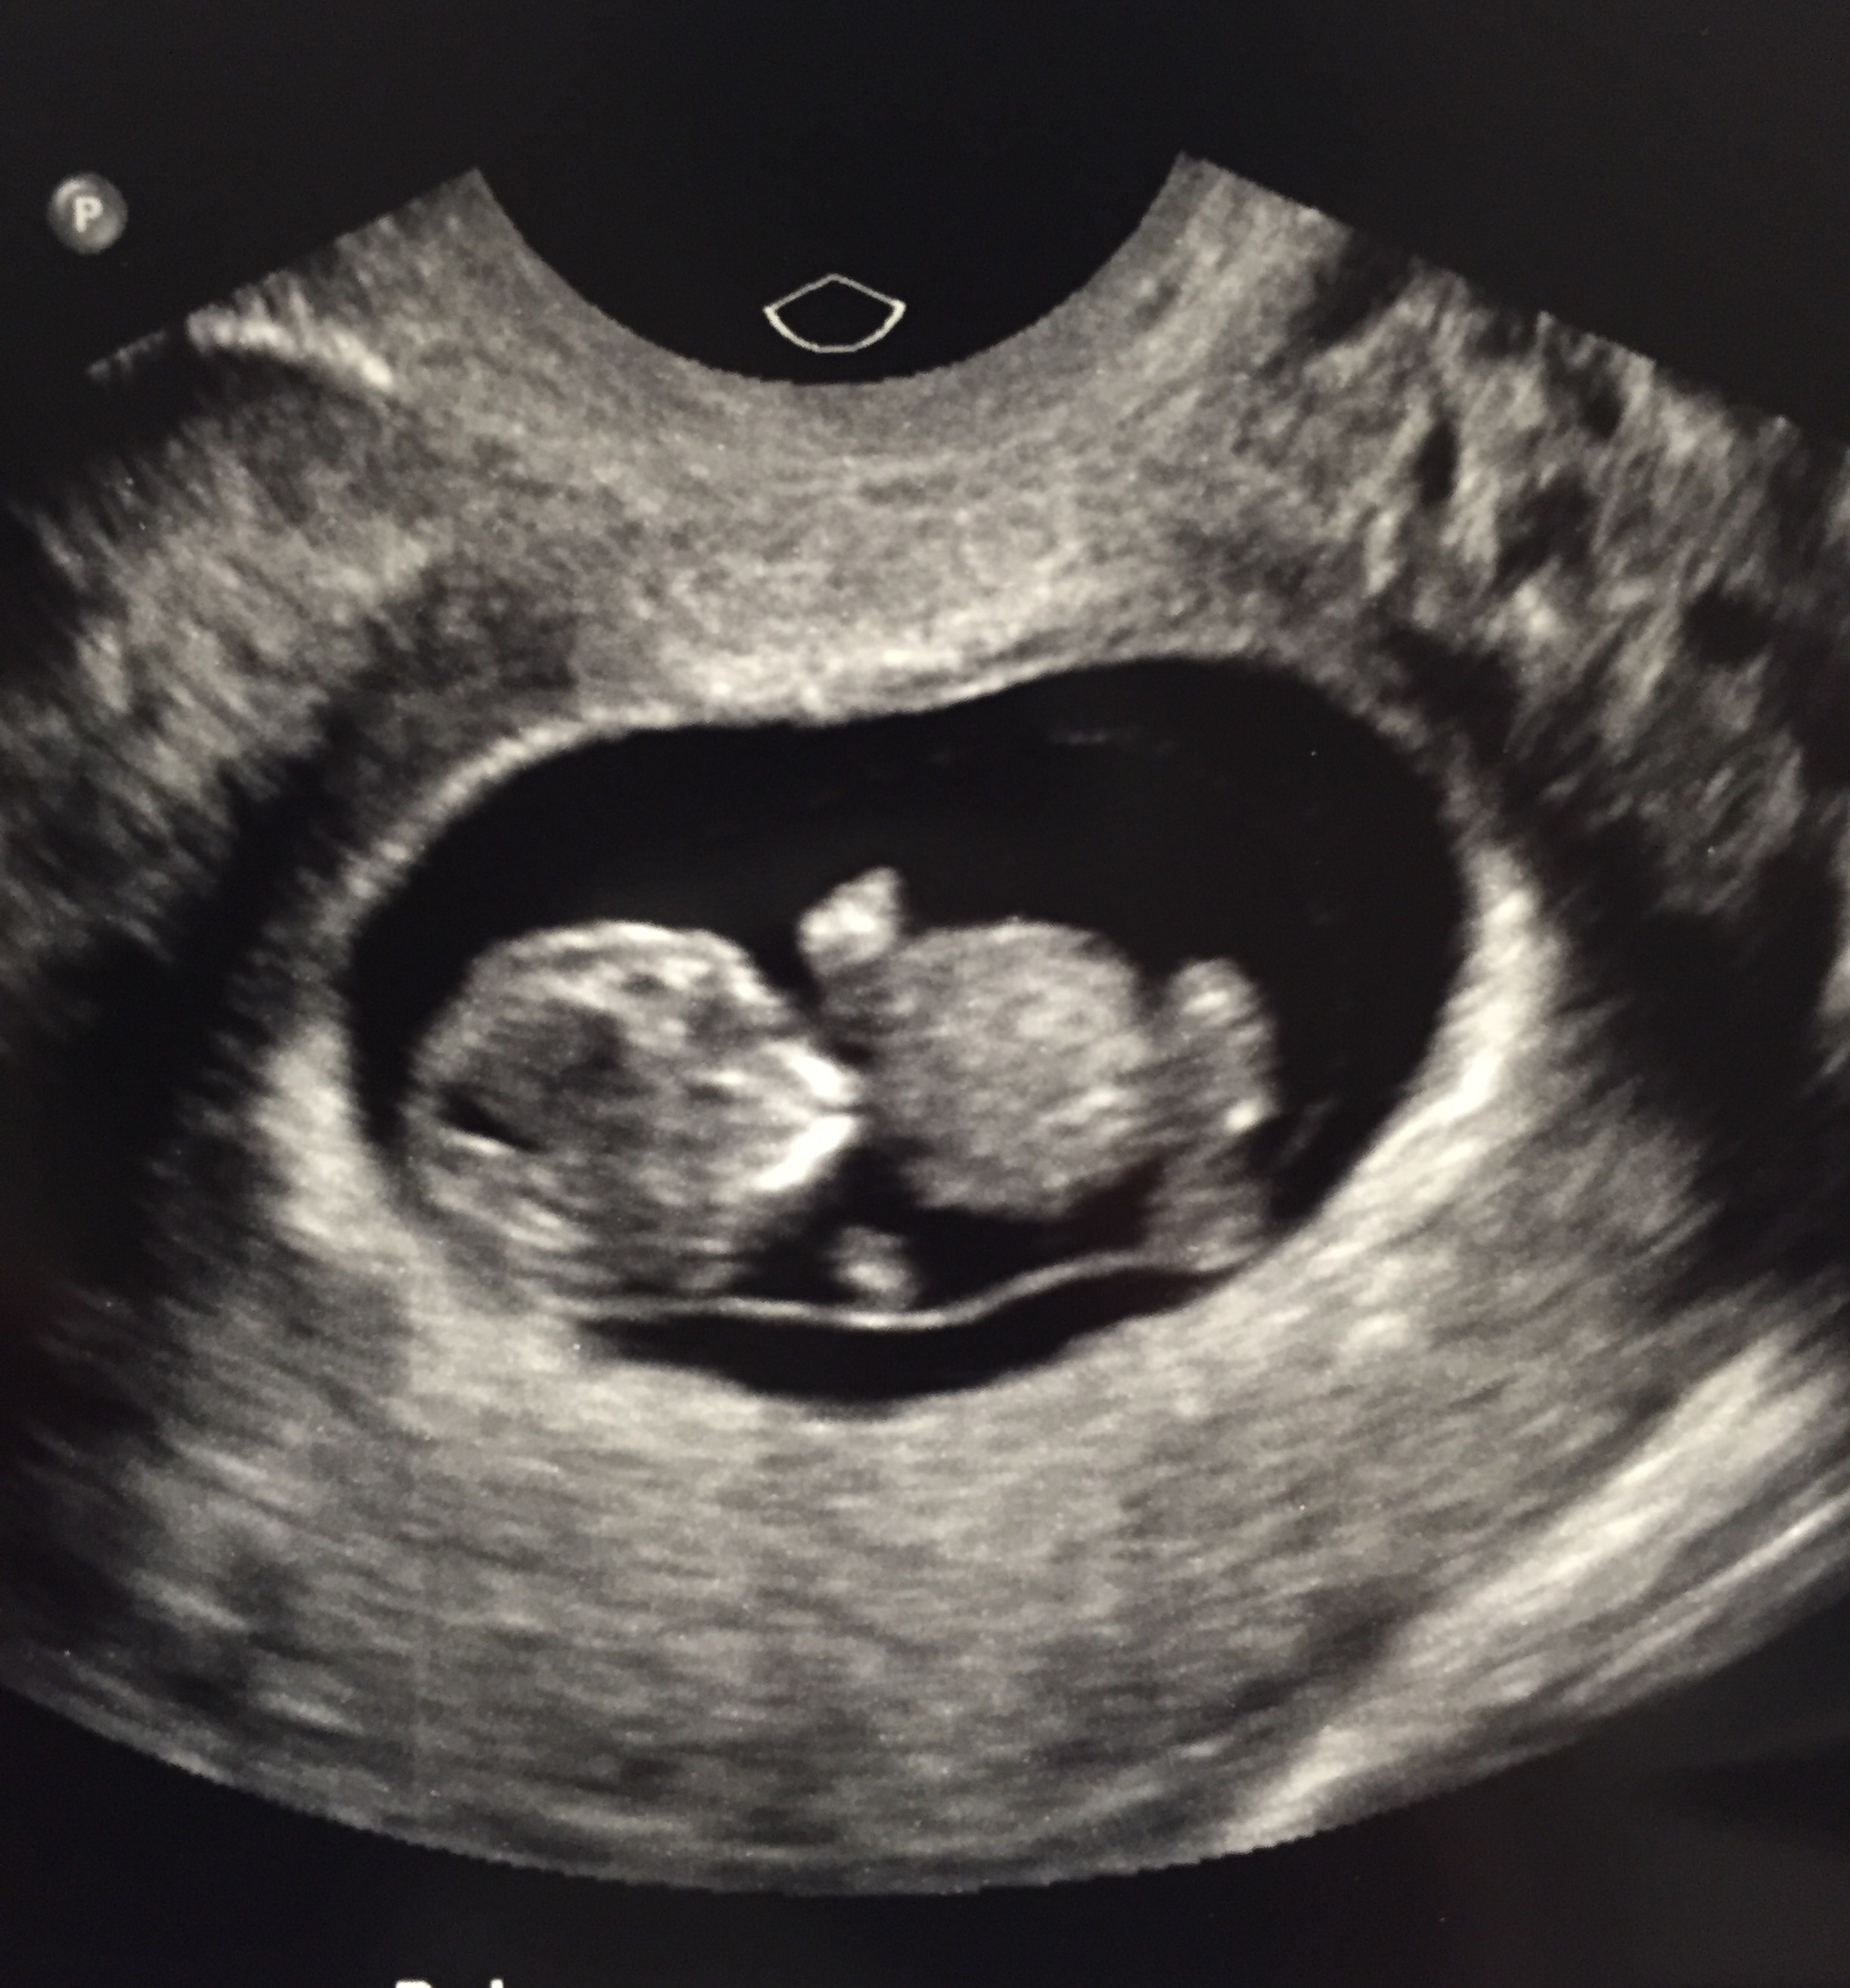

Finally got our first ultrasound. Went in thinking I was 12+4 and it turns out I am actually measuring at 13+6. My due date got pushed up from November 8 to October 30! We have a very squirmy little thumb sucker. So incredible.